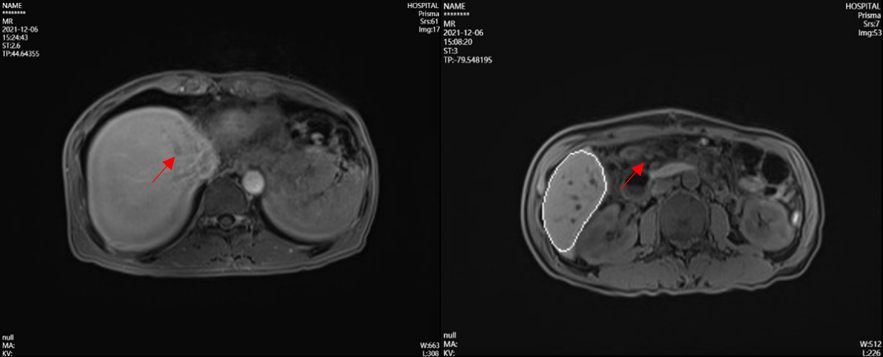

2021年12月,MR显示肝脏复发病灶,肠系膜淋巴结考虑转移(见图2)。

图2 MR结果